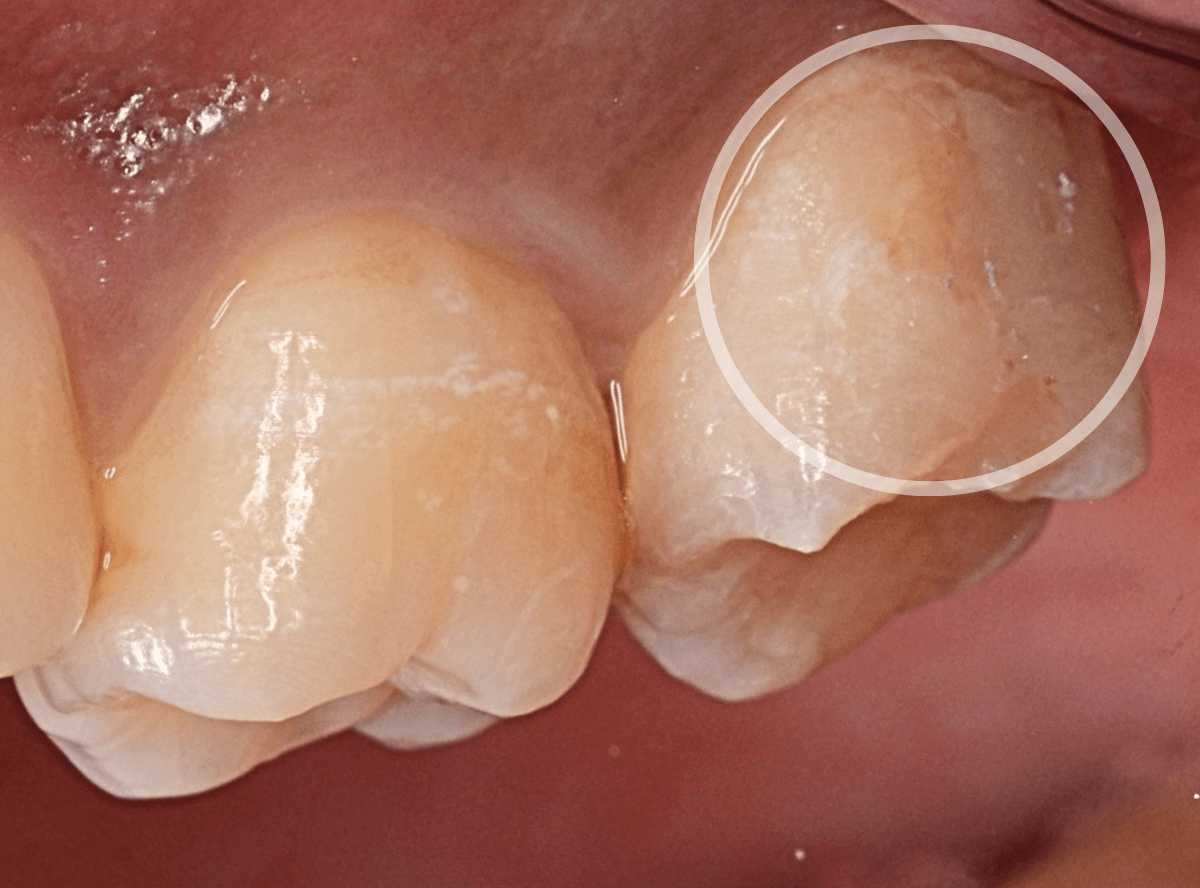

「歯の側面が虫歯になってしみる」という訴えで来院された患者さんです。

これは、くさび状欠損といって、歯ブラシ圧の強すぎや歯ぎしりなどが原因で歯の側面が摩耗した状態の部分が若干の虫歯になった状態です。

くさび状欠損は、知覚過敏の原因になる事が多いですが、症状がなければ経過観察にする事も多いです。

今回は、表面が虫歯になっている事と、しみるという症状があるため、治療をする事になりました。

麻酔をして、虫歯の部分を除去します。

幸い、表面上の虫歯でしたので、歯の削除量は少なく済みました。

削った部分にレジンを充填して終わりです。

これでしみる症状は改善されると思いますが、麻酔をしているので、確認は次回来院時になります。